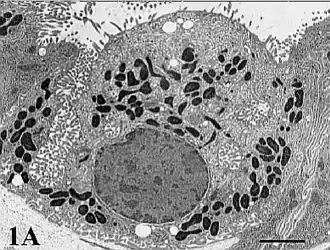

![]() Célula parietal gástrica microscopio electrónico | ||

Mediante la microscopía electrónica se pueden observar las características propias de esta célula.

De forma piramidal, el citoplasma de las células parietales está repleto de mitocondrias, con abundantes lisosomas y un sistema tubulovesicular prominente.

La nanotomografía[nb 1] evidencia redes intrincadas de mitocondrias, que se distribuyen de manera uniforme por todo el citoplasma. Estos orgánulos numerosos tienen crestas compactas y una matriz densa que contiene partículas opacas.

Los lisosomas son abundantes aproximadamente esferoides, se encuentran adyacentes a las mitocondrias.

Los orgánulos de membrana tubular y vesicular (tubulovesículas) se distribuyen por todo el citoplasma de las células parietales.